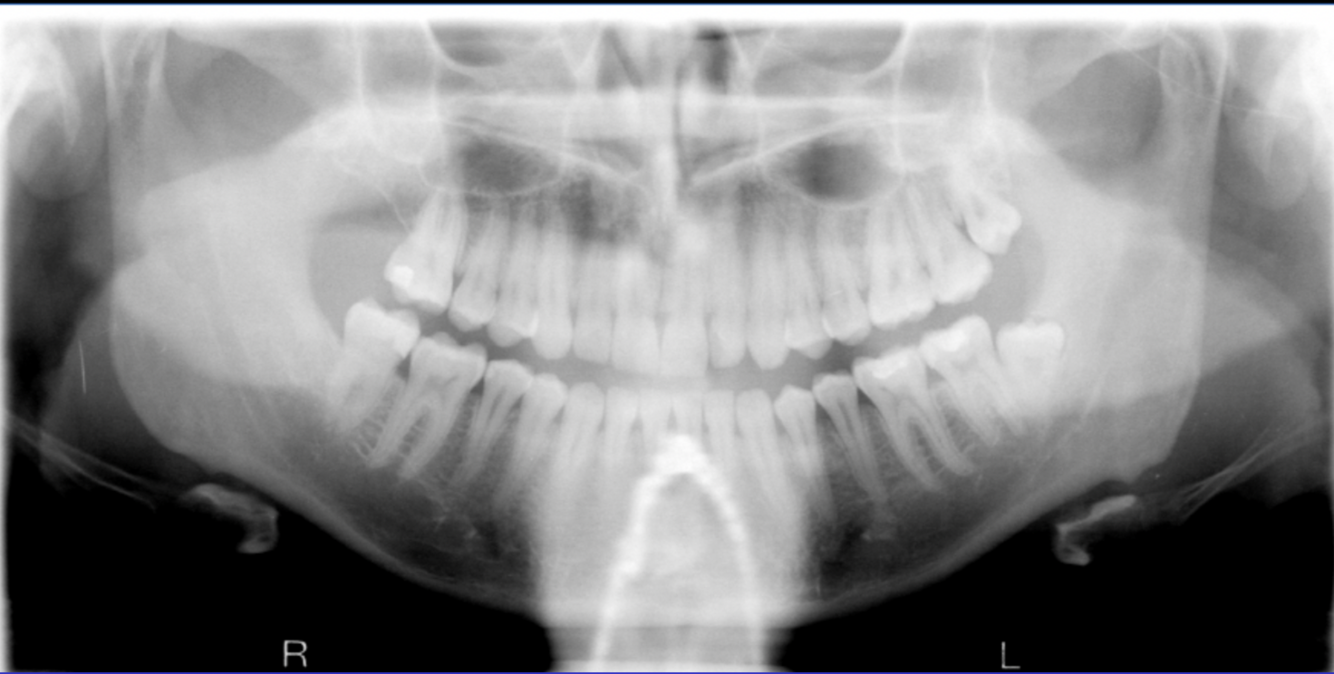

What errors can be seen in the following radiograph? What is the cause of these errors?

A

Anterior teeth are narrowed and blurred

(notice posterior teeth appear normal)

Cause: Too far forward